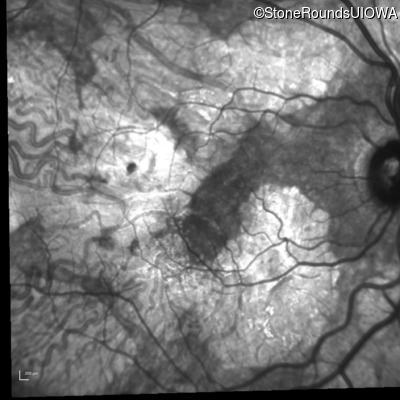

AR Stargardt Disease (IIA)

Age at visit: 54 years

Diagnosis & molecular findings

Disease Gene Allele 1 variant(s) Allele 2 variant(s) Inheritance mode

AR Stargardt Disease ABCA4 Gly1507Arg GGG>AGG IVS42+1 G>A AR